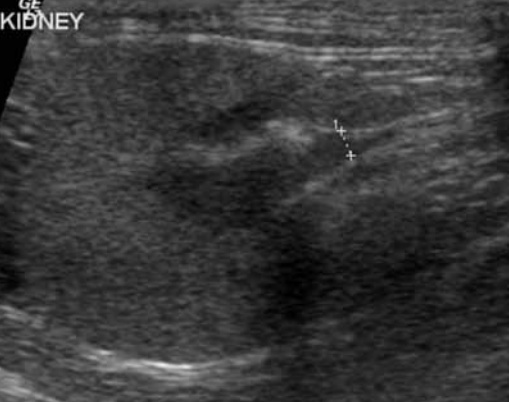

6-2. 신우신염(Pyelonephritis)(그림 13)

신우신염은 세균 감염에 의한 신우 및 신실질 염증입니다.

초음파 영상 소견은 신우에 경미한 확장, 근위 요관의 확장, 무에코 또는 고에코 잔사(debris), 둔화되고 불명확한 신배를 보입니다. 급성 신우신염에서는 신우 및 요관 확장이 없을 수도 있습니다.

신장 크기는 급성에서 정상 또는 증가, 만성에서는 정상 또는 감소를 보이며, 추가 소견으로는 피질의 고에코화, 신장 능선(renal crest)을 따라 고에코 선을 보이고, 피질 또는 수질 내 국소의 고에코 혹은 저에코 병변, 피질–수질 경계 불분명 등이 있습니다. 영상 소견은 매우 다양하며 비특이적입니다.